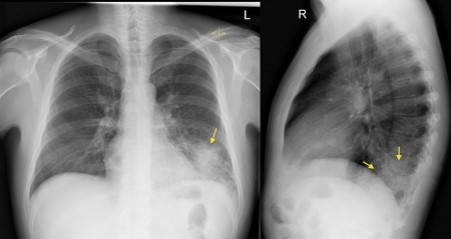

7 year old previously healthy Hispanic male presented to an emergency department with 1 week of a non-productive cough and intermittent fevers measured at home to 103.5°F

View: PA/lateral

DX: pneumonia